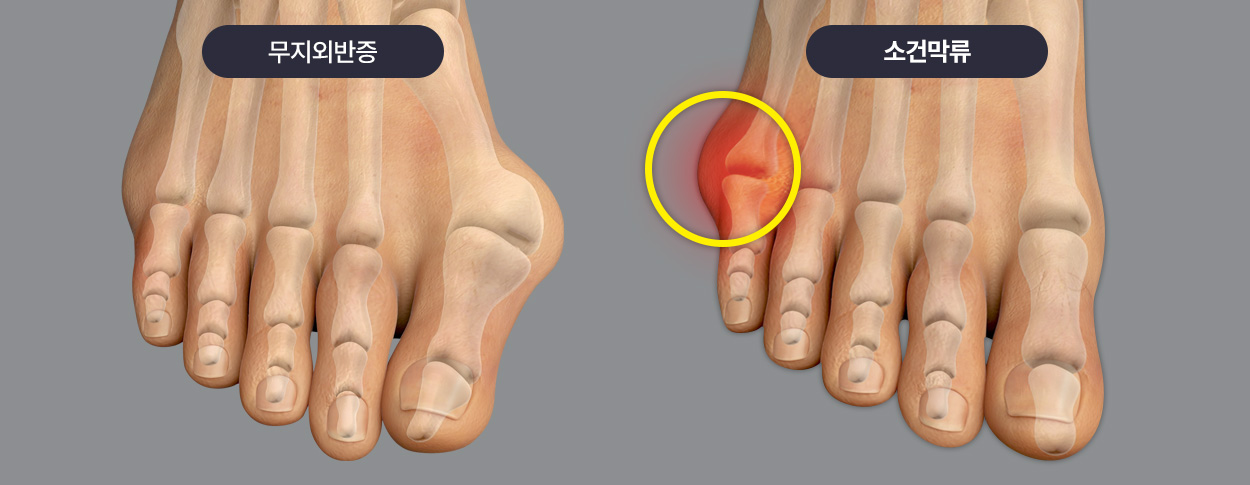

소건막류는 새끼발가락 관절의 뿌리 부분이 바깥쪽으로 튀어나오면서 발생하는 변형입니다.

이 튀어나온 부분이 신발과 마찰을 일으켜 통증, 염증, 굳은살 등을 유발할 수 있습니다.

엄지발가락이 휘면서 돌출되는 무지외반증처럼 새끼발가락쪽에 외반 변형이 생긴 것을 의미합니다.